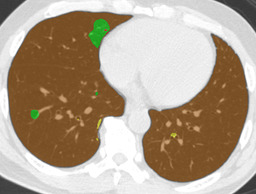

EMP \blacksquare

Refer to caption Refer to caption Refer to caption Refer to caption

0.793 0.847 0.815

Figure 4: Average results and dice coefficients for each DLD pattern. Automated segmentation results are superimposed with colors. For each DLD pattern, the slice that gave the median dice coefficient for the proposed method with λ=0.1𝜆0.1\lambda=0.1 was chosen to represent the average result. Note that although CNN performed multi-class segmentation, only one DLD pattern per slice was taken into account for the evaluation.